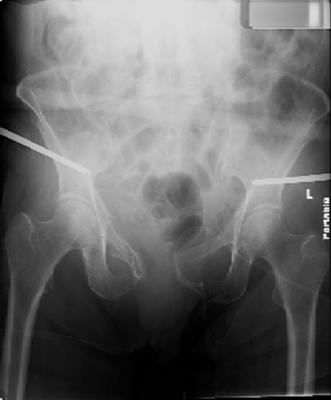

injuries are limited to the pelvis. left rami open and visible in a 10cm vertical laceration just lateral to left labia majora. wound is grossly clean. no vaginal and no urinary issues. CT scan shows widening of both SI joints anteriorly but I think this is vertically stable pattern.

pt treated that night with I/D and supra-acetabular frame to close the ring. consideration was given for SI screws bilateraly, but given time of night and other factors decision made not to proceed.

so the question is what next operatively if anything? concerns are infection, nonunion anteriorly and possible incompetence of the pelvic floor which may lead to prolapse issues. right rami are comminuted and plating may entail ilioinguinal approach to extend plate laterally to right iliac wing. retrograde screw up right rami is an option but I am not convinced it will add much. adding SI screws very doable, but major concern is restoring anterior ring. so far wound is clean and closed over a drain, and I have no plans to open it back up and wash again.

maintaining pelvic alignment in ex-fix in 70 yo female for any length of time may be challenging.

any thoughts? would anyone plate the pubic symphysis to close the gap and leave the more lateral rami fractures alone? the most recent pelvic case on this website involved pts with suprapubic catheters and antibiotic options including resorbable beads. I wonder how many people would plate and place antibiotic beads. thanks.